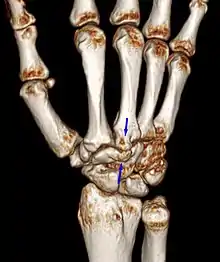

Carpal boss VR-3D-Reconstruction

The joint between the index metacarpal and the capitate is a fibrous non-mobile joint. Some people have a gene that leads to this growth. It looks like arthritis (bone spurs on each side of the joint) on X-ray. It looks like a ganglion on the hand, but more towards the fingertips.

The carpometacarpal joint is usually found at the base of the second and third metacarpal bones at the point where they meet the small bones of the wrist.[2]